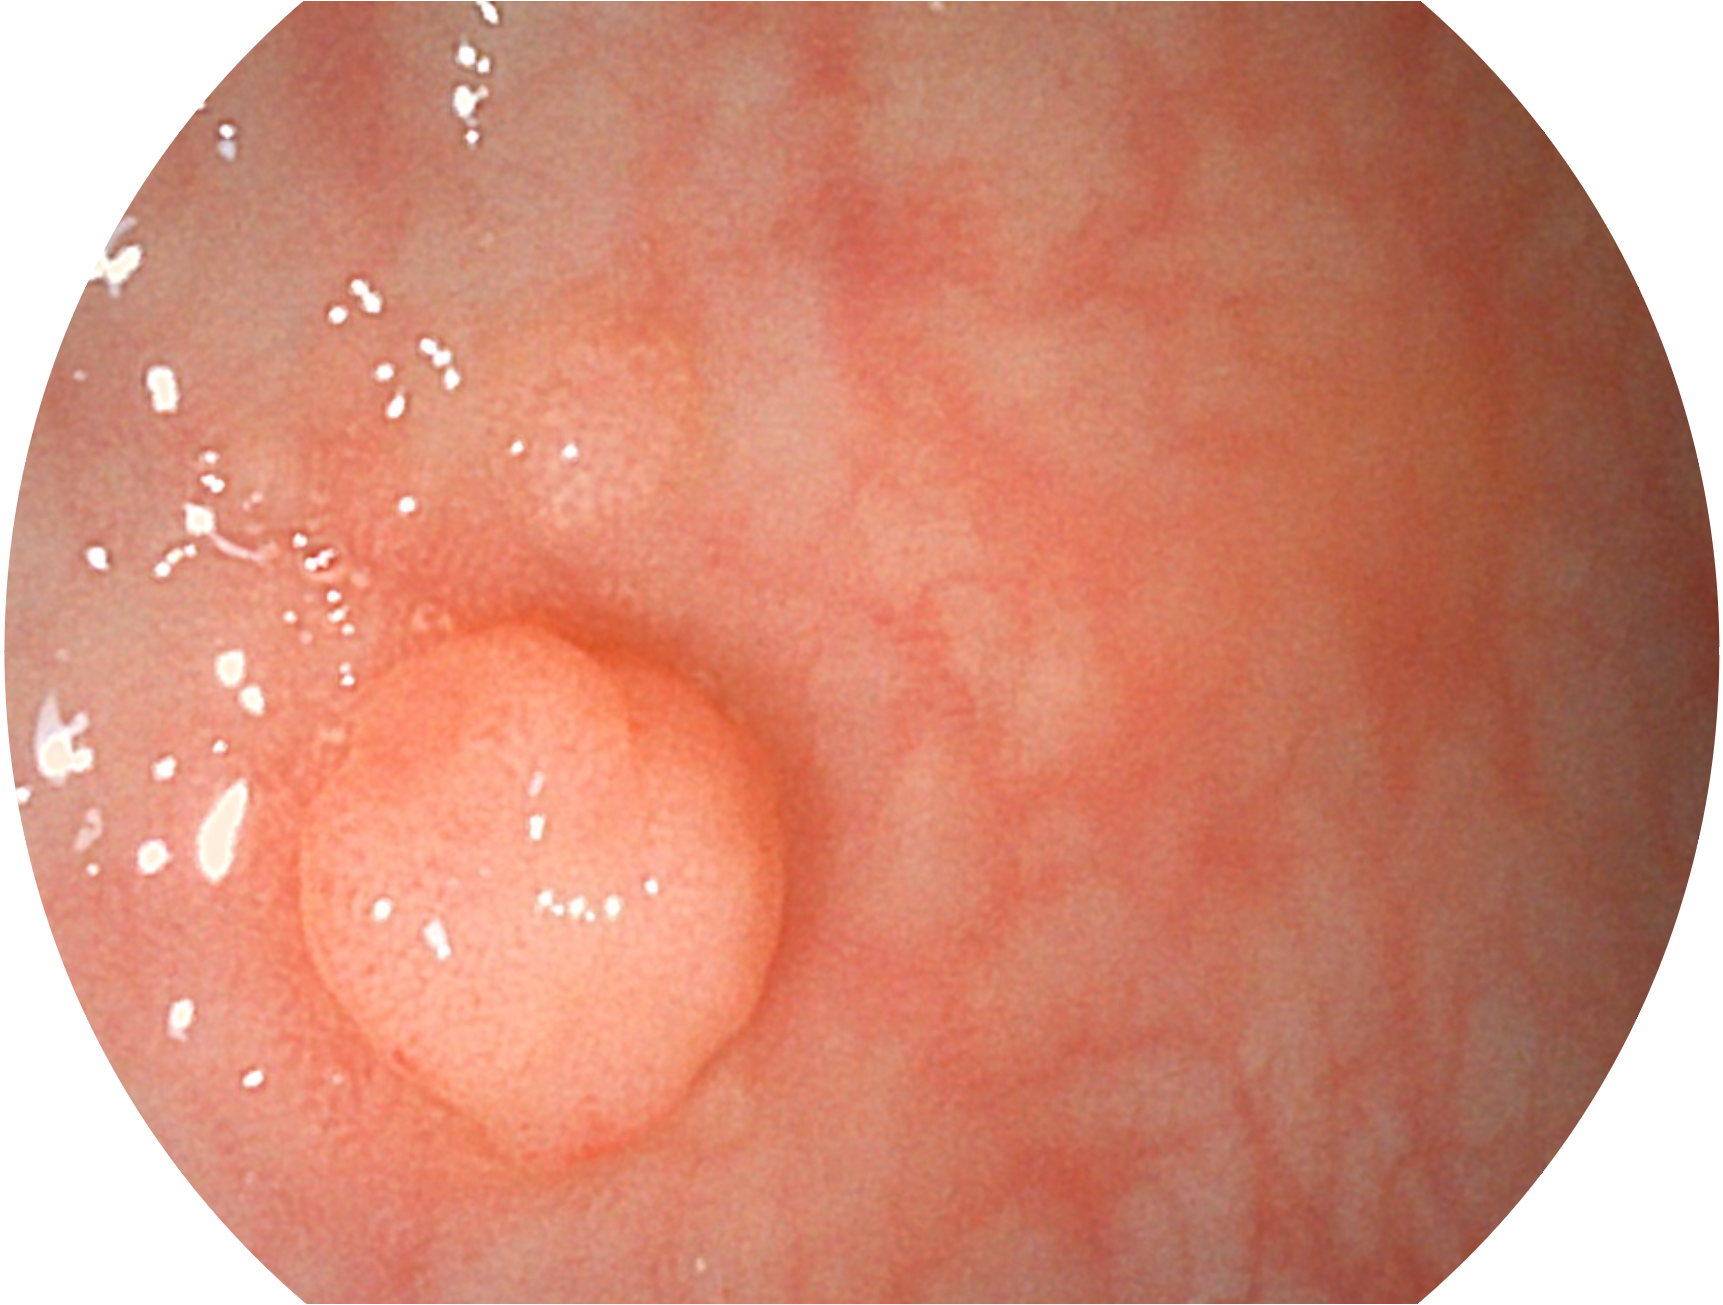

MILE米乐集团官网新开发的内镜染色技术,主要是基于多波长LED 光源的开发,VLS-55Q 四波长LED 光源是由四个不同颜色的LED光按照相应照明模式所规定的特定发光比例进行合束后形成,合束后形成的照明光的光谱由红光、绿光、蓝光及蓝紫光这四个不同的波段范围构成。具有更高光谱自由度,通过光谱比例的控制,实现了聚谱成像技术,英文全称为“Spectral Focused Imaging, SFI”,缩写为“SFI”和光电复合染色成像技术,英文全称为“Versatile Intelligent Staining Technology, VIST”,缩写为“VIST”。